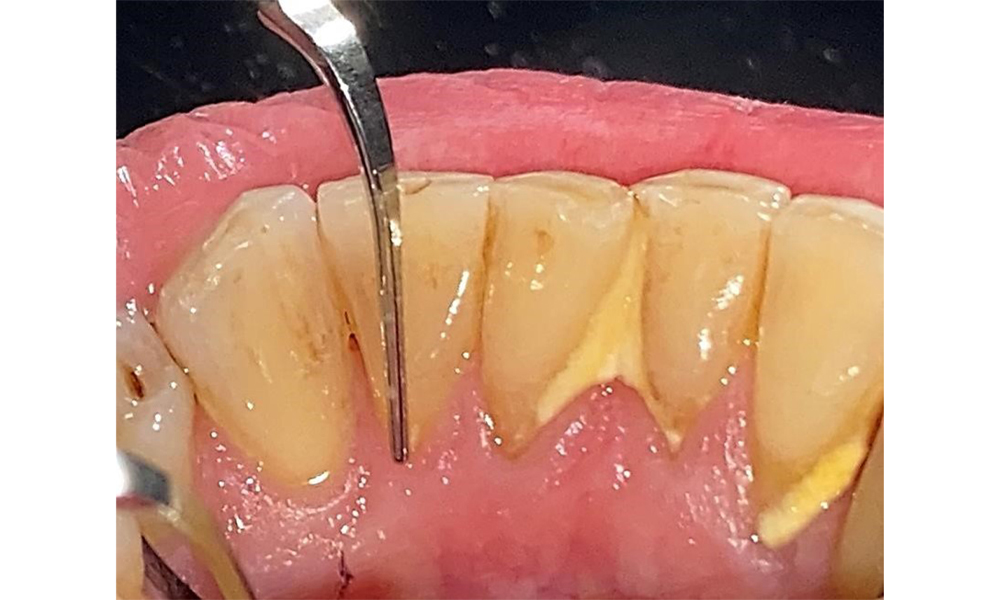

The documentation of periodontal findings, including pocket depth probing and bleeding status, is mandatory during each dental appointment due to the presence of periodontitis (Fig. 8). This will record the individual therapeutic needs and facilitate a rapid response to any progression of the pre-existing periodontitis.

Probing to document the findings in tooth 27 mesiopalatal.

Fig. 8: Probing to document the findings in tooth 27 mesiopalatal. © Dr R. Krapf

There are no limitations regarding the choice of instrumentation methods. Regular supragingival and subgingival instrumentation is essential to prevent disease progression due to the pre-existing periodontitis and high risk of recurrence. There are no limitations placed on the selection of instruments for mechanical biofilm removal from a general medical perspective, and removal should be performed as needed. Hard and mineralized plaque, such as calculus and concretions, should be removed using manual instruments or sonic/ultrasonic scalers (Fig. 9) (8, 9).

Use an ultrasonic tip to remove hard, mineralized plaque (Proxeo Ultra scaler with the Perio tip, W&H, shown here).

Fig. 9: Use an ultrasonic tip to remove hard, mineralized plaque (Proxeo Ultra scaler with the Perio tip, W&H, shown here). © Dr R. Krapf